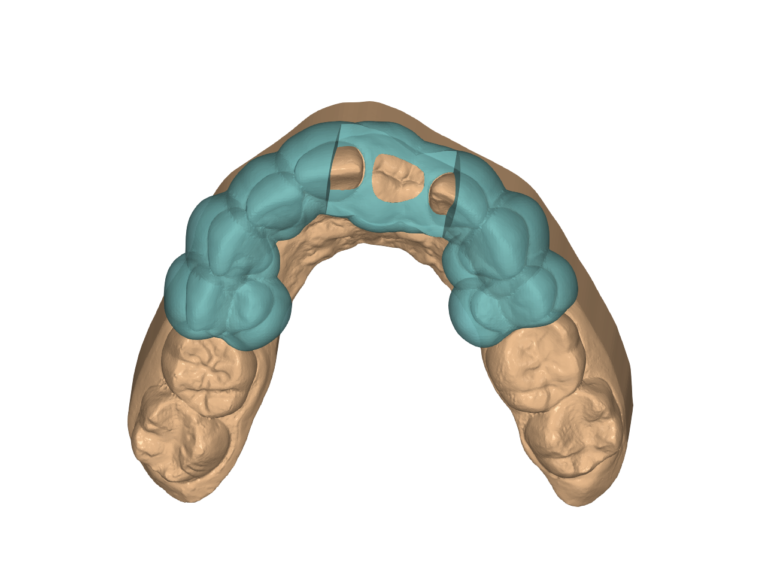

Stackable Guide

These guides are used for full-arch FP1 and FP3 cases and can be gingiva-supported or bone-supported. These cases are complex and typically performed by Dental Specialists. We use JB Dental Lab in the USA for the design and manufacture of the final prosthesis, but we can manufacture the temporary prosthesis locally. Feel free to use your preferred lab.